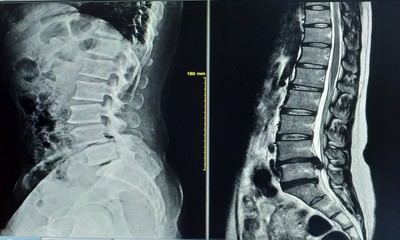

2. レントゲン検査

レントゲン検査

骨の変化の程度や骨折の有無、腫瘍が疑われる所見がないかを確認します。あわせて、骨粗しょう症に関連する変化がみられないかも確認します。

診察では、レントゲンやエコー、MRIなどの検査結果に加え、姿勢や日常動作の様子も確認しながら、現在の状態を把握していきます。

その内容をもとに、症状や経過、生活状況を踏まえた治療やリハビリテーションの方針についてご説明し、今後の進め方をご案内しています。